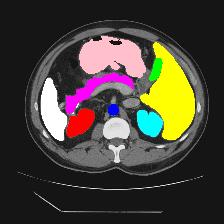

Medical image segmentation is one of the most fundamental tasks concerning medical information analysis. Various solutions have been proposed so far, including many deep learning-based techniques, such as U-Net, FC-DenseNet, etc. However, high-precision medical image segmentation remains a highly challenging task due to the existence of inherent magnification and distortion in medical images as well as the presence of lesions with similar density to normal tissues. In this paper, we propose TFCNs (Transformers for Fully Convolutional denseNets) to tackle the problem by introducing ResLinear-Transformer (RL-Transformer) and Convolutional Linear Attention Block (CLAB) to FC-DenseNet. TFCNs is not only able to utilize more latent information from the CT images for feature extraction, but also can capture and disseminate semantic features and filter non-semantic features more effectively through the CLAB module. Our experimental results show that TFCNs can achieve state-of-the-art performance with dice scores of 83.72\% on the Synapse dataset. In addition, we evaluate the robustness of TFCNs for lesion area effects on the COVID-19 public datasets. The Python code will be made publicly available on https://github.com/HUANGLIZI/TFCNs.